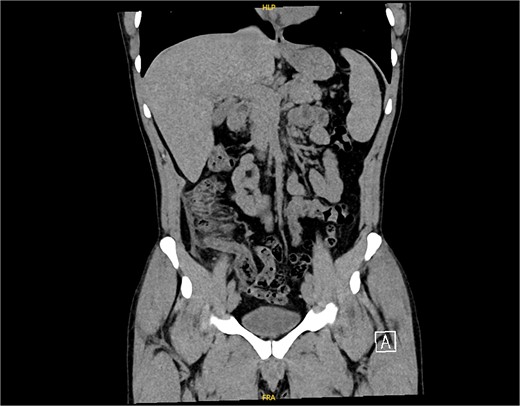

On examination, the patient was alert, oriented, and vitally stable. Abdominal examination revealed mild tenderness and rebound tenderness in the right iliac fossa. Laboratory investigations showed normal leukocyte counts and mildly elevated C-reactive proteins (38). An abdominal ultrasound suggested acute appendicitis or terminal ileitis (Fig. 1), prompting a CT scan despite the patient’s allergy to contrast.

An ultrasound picture showing tubular-like structure surrounded by edematous fluid.

The non-contrast CT scan revealed a retrocecal appendix measuring 11 mm in diameter, with periappendiceal fluid and fat smudging, and reactive thickening of the cecum, indicating uncomplicated acute appendicitis. The patient was admitted to the surgical department and scheduled for a laparoscopic appendectomy (Figs 2 and 3).